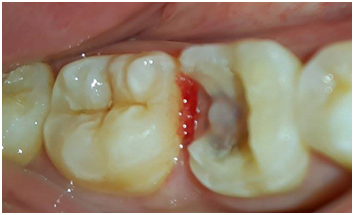

A 25years old male patient with unremarkable medical history, presented to the department of fixed prosthodontics with esthetic and functional demand. His chief complaint was to replace the defective amalgam restoration on the first right mandibular molar (Figure 1). A comprehensive clinical examination revealed good hygiene, a defective amalgam restoration on the first right mandibular molar, which caused a papilla inflammation between the 46 and the 47.

Figure 1 Defective amalgam restoration on the first right.